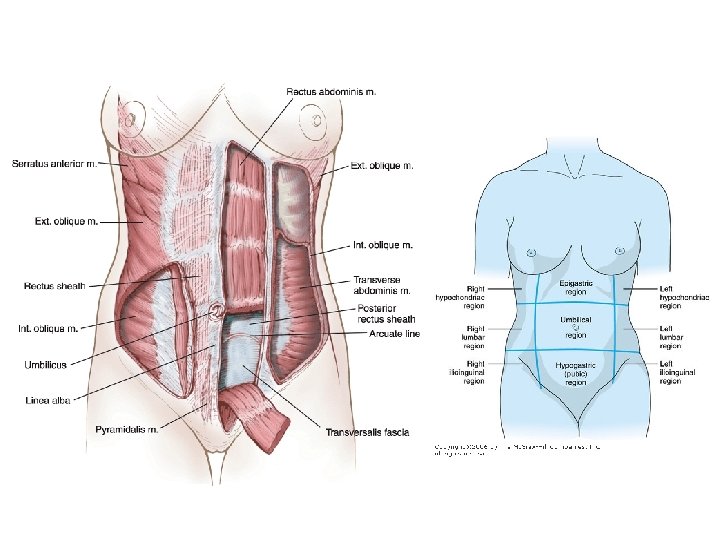

Abdominal Wall • • Skin Subcutaneous fat (superficial fascia), which below the navel can be considered as two layers: – Camper’s fascia; the superficial layer containing fat, – Scarpa’s fascia; fibroelastic membrane. • Muscles, The abdominal muscular wall can be considered a group of 4 paired muscles along with their aponeurosis: – The three lateral muscles (from superficial to deep) are the • External abdominal oblique • Internal abdominal oblique • Transversus abdominis muscle – Medially muscles are the: • Rectus Abdominis • Pyramidalis muscles • • Preperitoneal fat Peritoneum – Parietal peritoneum of anterior abdominal wall • Visceral peritoneum investing the viscera